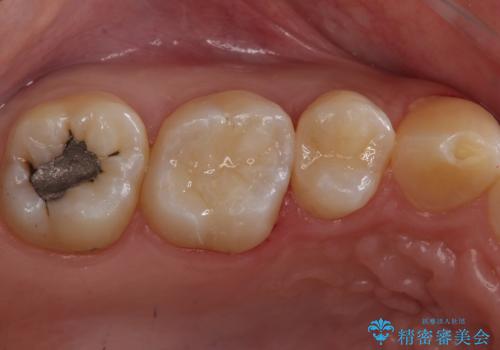

まだ虫歯が大きくなる前に処置をすることができたため神経の治療をせずに済みました。

歯と歯の間・適合の悪い修復物とその歯の間は虫歯ができることが多い場所になります。

修復物と歯の間の虫歯は、丁寧な虫歯除去と精密な修復物を装着することで予防することができます。